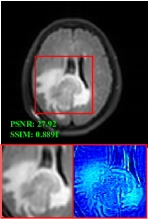

Figure 5 provides the qualitative comparison of the various methods on the four datasets at a scale of 4. The top, second, third, and bottom rows are the SR results under the FastMRI, clinical brain, clinical tumor and clinical pelvic datasets, respectively. The red boxes indicate the zoom-in region of complicated anatomical structures along with their corresponding error maps. Note that the brighter textures in the error maps, the lower the quality of the reconstructed images. As can be seen, compared to methods based on Transformers and CNNs, diffusion-based methods like DisC-Diff and DiffMSR (Ours) are capable of reconstructing high-realistic images with promising reconstruction metric scores (PSNR and SSIM). Nevertheless, while DisC-Diff can reconstruct high-precision MR images, it does not preserve the structure present in the original HR images, introducing some additional information that can affect medical diagnosis. In contrast, our method combines DM and PLWformer, which can preserve the original image’s structure while restoring high-frequency information.

In this section, we present more visual qualitative comparisons. Figures 8, 9, 10, and 11 show the reconstruction results of each method in FastMRI, clinical brain, clinical tumor, and clinical pelvic, respectively. As can be seen, although DisC-Diff can reconstruct MR images with high-frequency information, it fails to preserve the structure and content of the original Target HR image effectively, resulting in image distortion. In contrast, our proposed DiffMSR can restore high-frequency information while preserving the structure of the original HR image, indicating the effectiveness of the joint use of DM and PLWformer.